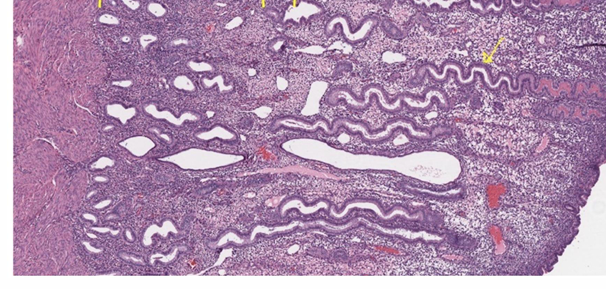

uterine anatomy